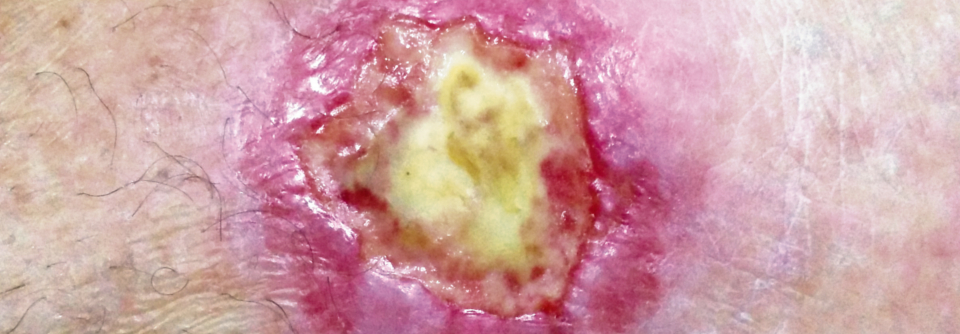

Die periphere arterielle Verschlusskrankheit ist Ausdruck einer generalisierten Atherosklerose. Die periphere arterielle Verschlusskrankheit ist Ausdruck einer generalisierten Atherosklerose. © iStock/Mindaugas_Kurmis

Die periphere arterielle Verschlusskrankheit (PAVK) ist Ausdruck einer generalisierten Atherosklerose. Patienten mit schweren Extremitätenmanifestationen oder weiteren internistischen Komorbiditäten erleiden überproportional häufig kardio- bzw. peripher-vaskuläre Komplikationen.